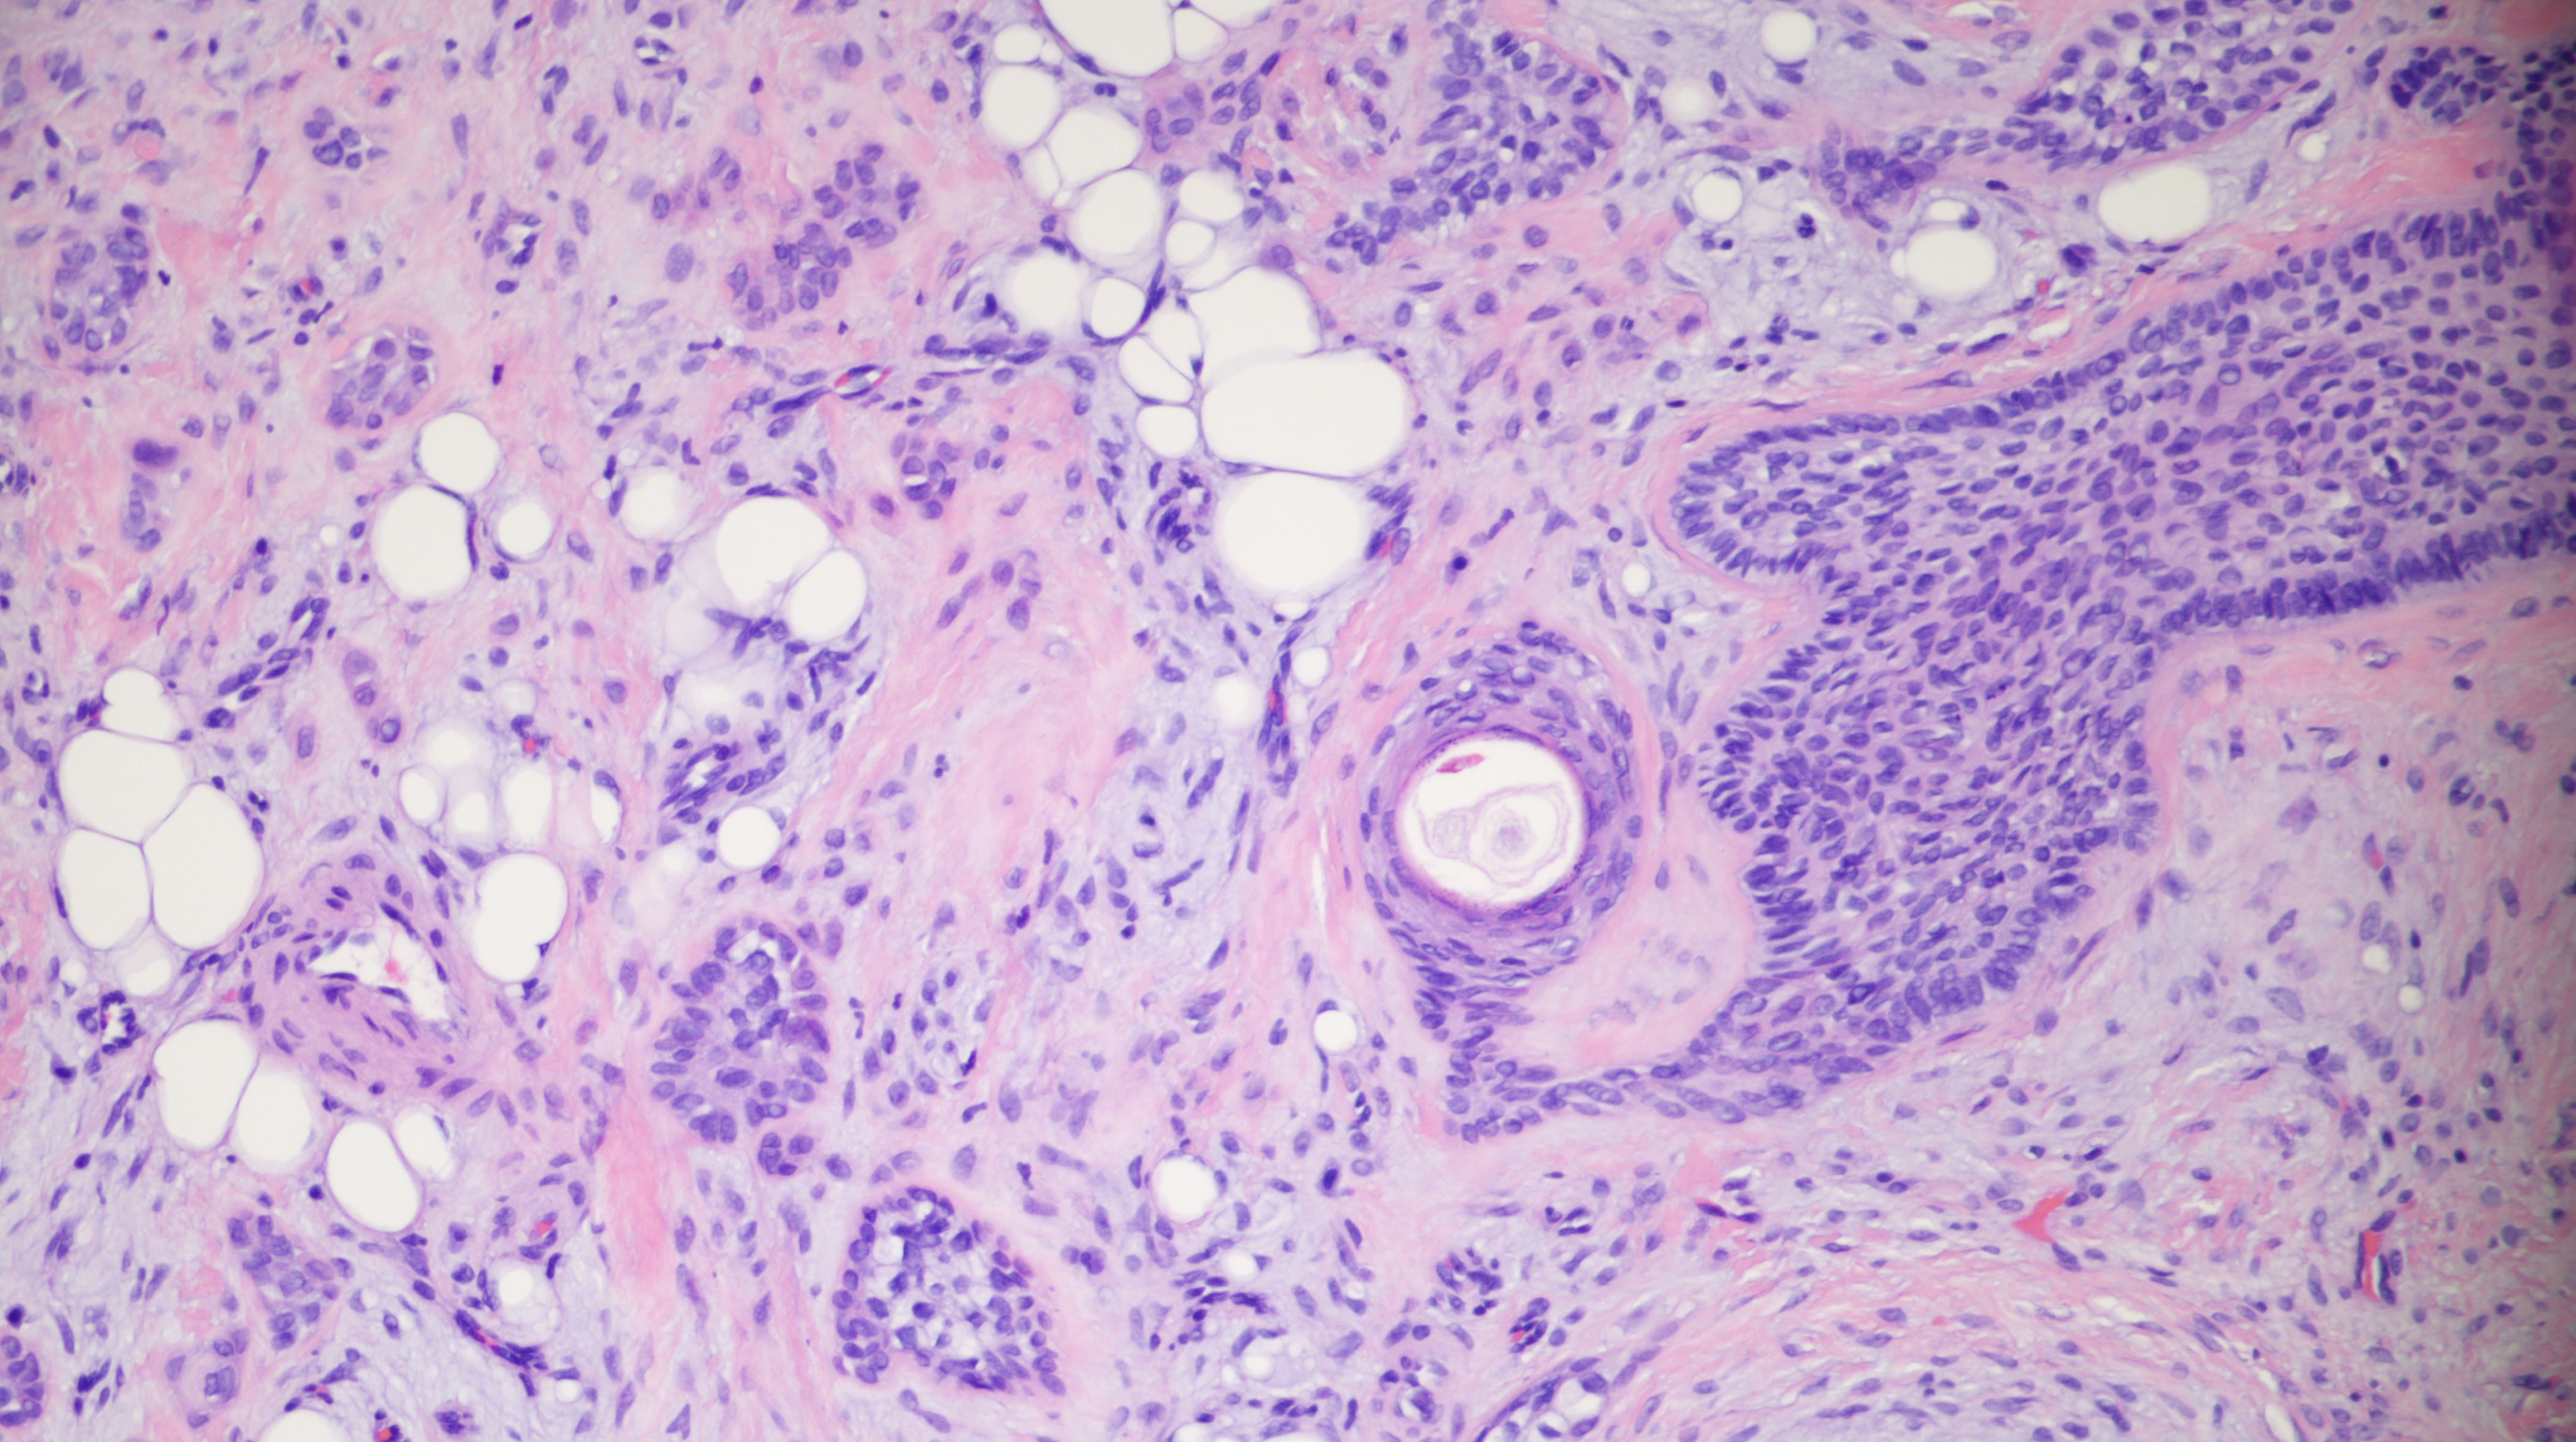

60-year-old man with an upper lip nodule.